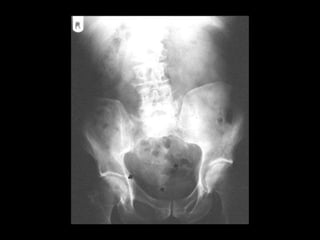

CT

Peritoneal calcifications